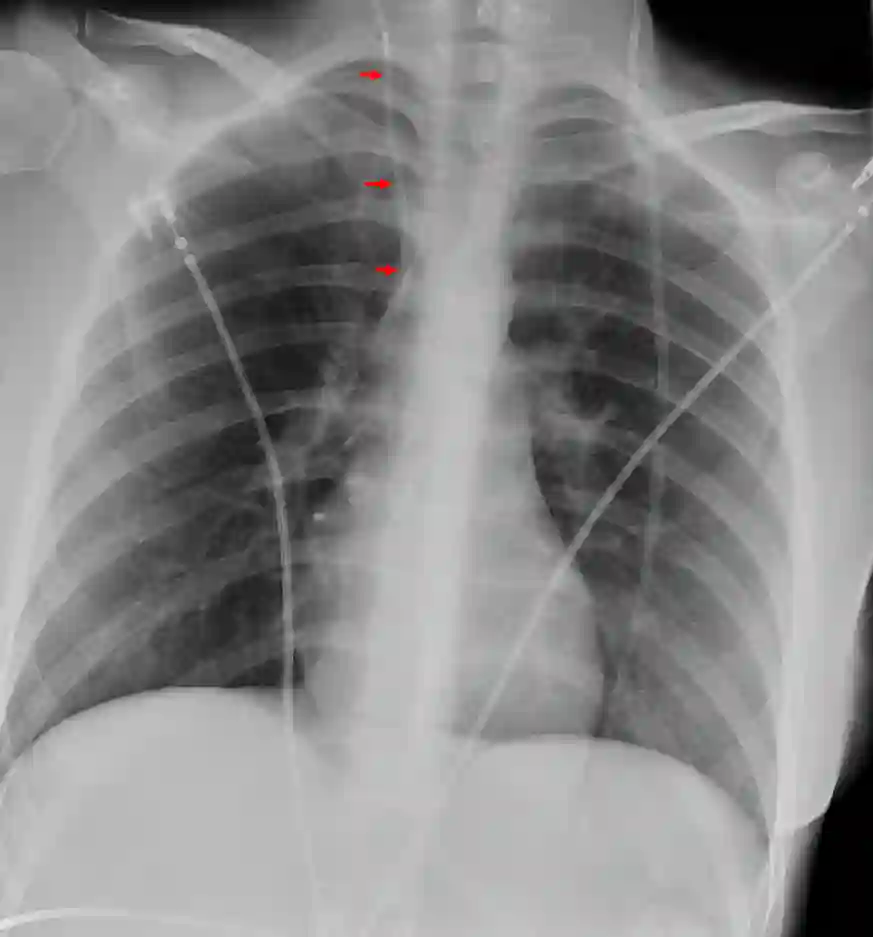

Röntgenbild eines VA-Shunts

Thoraxröntgen mit Darstellung eines VA-Shunts im Röntgenbild (roter Pfeil).